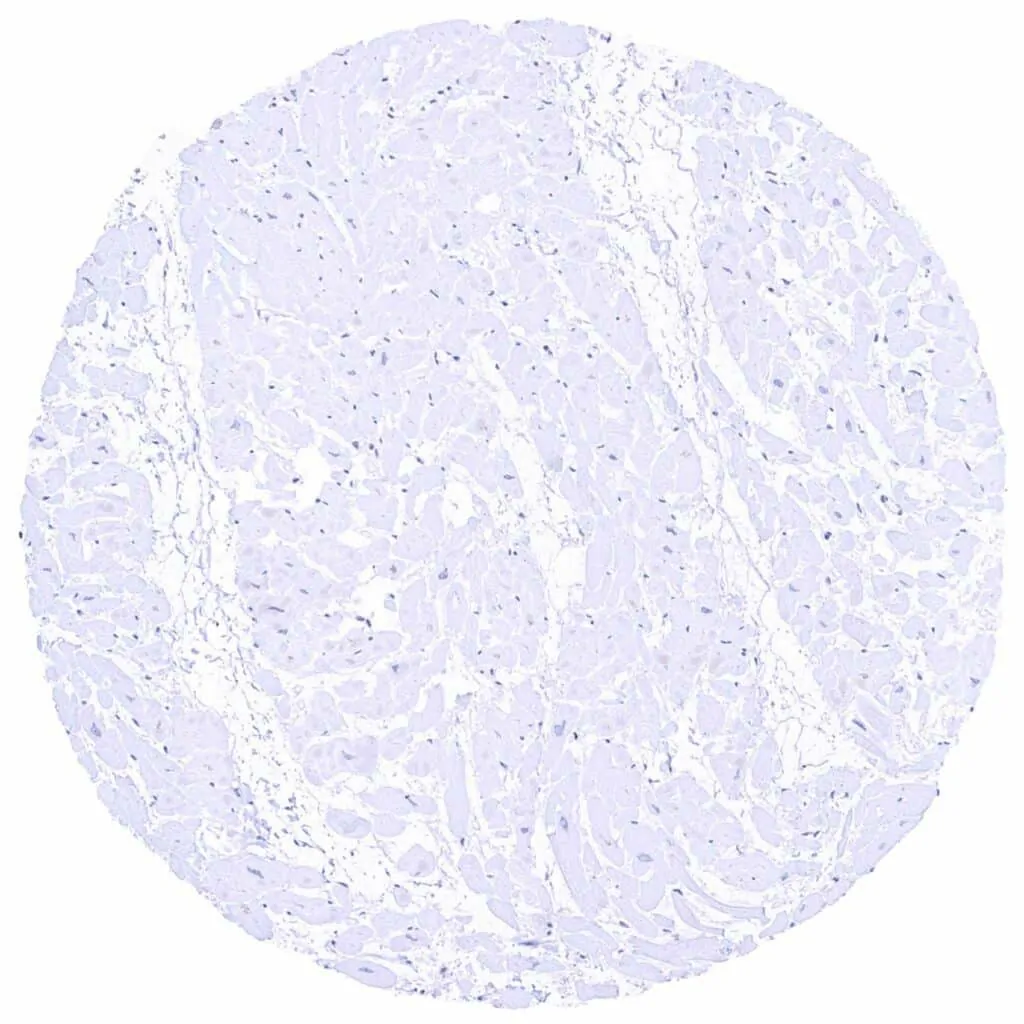

Heart muscle